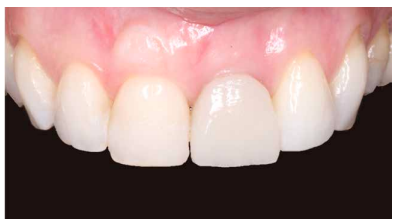

Caso clínico: Se presenta el caso de una paciente mujer de 32 años de edad, que acude por presentar una posible fractura radicular del incisivo central superior izquierdo (ICSI), acompañada de la aparición de un absceso periodontal en la región del fondo de vestíbulo de dicho diente. Tras llevar a cabo la exploración clínica y radiológica, se establece que el pronóstico del ICSI es desfavorable para llevar a cabo un tratamiento conservador del mismo. Tras la valoración de las características clínicas del caso presente, el plan de tratamiento se inclinó por la realización de la exodoncia del ICSI con la colocación simultánea de un IOI postextracción y la carga inmediata con una prótesis provisional del mismo.

Clinical case: We present the case of a 32-year-old female patient who presented with a possible root fracture of the upper left central incisor (ULCI), accompanied by the appearance of a periodontal abscess in the region of the bottom of the vestibule of said tooth. After carrying out the clinical and radiological examination, it is established that the ULCI prognosis is unfavourable for carrying out conservative treatment of the tooth. After assessing the clinical characteristics of the present case, the chosen treatment plan was to extract the ULCI with the simultaneous placement of a post-extraction osseointegrated implant (OII) and immediate loading of a provisional prosthesis on the implant.

Los beneficios de la carga inmediata incluyen una reducción notable de las intervenciones quirúrgicas, una menor dilatación temporal del tratamiento e incluso un mejor bienestar psicológico y social para el paciente. En casos con importante compromiso estético, la carga inmediata o la provisionalización inmediata, añadida a la colocación inmediata postextracción del IOI permiten minimizar las alteraciones derivadas de la pérdida dental, manteniendo el perfil de emergencia, contorno de tejidos blandos y las papilas gingivales5-7.